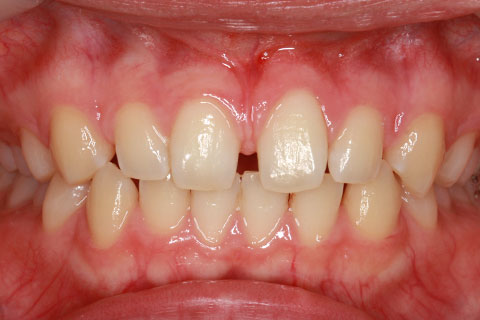

• オールセラミックの症例2

治療前

治療後

年齢・性別

45歳男性

治療期間

2ヶ月

抜歯

なし

治療費

70.4万円

備考

前歯8本の歯列不正によるセラミック治療

治療内容

歯質を削除し、セラミック冠をセメント合着

施術の副作用(リスク)

知覚過敏、歯髄炎、荷重負担